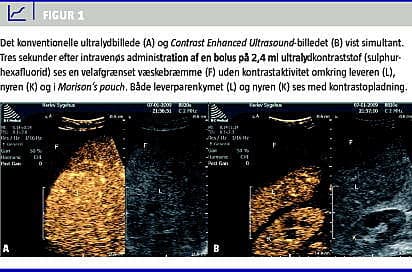

For at undersøge det nærmere blev der foretaget CEUS. I en i forvejen anlagt intravenøs adgang blev der givet en bolus på 2,4 ml ultralydkontraststof (sulphurhexafluorid) efterfulgt af 10 ml isotonisk saltvand. Det konventionelle UL-billedet blev vist simultant med CEUS-billedet på ultralydskannerens skærm. CEUS viste en velafgrænset bræmme uden kontrastaktivitet omkring leveren, i Morison's pouch og mellem tarmene (Figur 1 ).